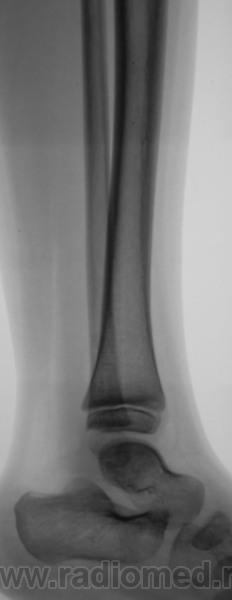

Ребенок из коммерческого областного ЛПУ был направлен по месту жительства, чтобы "доснять" остальные суставы. Выставлен диагноз ревматического полиартрита

Да нет. Правый локтевой какой-то "неискренний".

По мне так явные - деформация и суставной впадины и локтевого отростка. Природу не скажу. Тут приоритет за лабораторными данными.

И + склероз субхондральный.

И фрагментация локтевого отростка.

Точно НЕ ревматический процесс: "...Суставной хрящ в процесс не вовлекается, поэтому деформация суставов при ревматизме не происходит."

Конечно спокойно, спокойно везде, кроме правого локтевого сустава...

Дите же, артроз рано еще))) Да и признаков нету, остеофитов нету, щель не сужена, какой-то видимой перестройки костной ткани нету. При скудном анамнезе больше ничего не придумывается. Плюс есть фрагмент локтевого отростка, мог ребенок упасть или стукнутся об что-то.

Валентин Львович, думаю, вероятнее всего, это, все таки, ревматоидный артрит (и так бы и написал в протоколе, пусть утверждают обратное). Но такого ни разу не видел, поэтому с уверенностью утверждать не могу. Термин "вторичный" артрит для меня загадка.